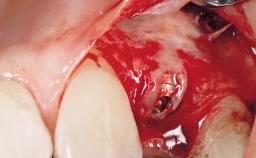

Immediate Flapless Placement of an Implant in a Maxillary Left Central Incisor Site

A 42-year-old female patient was referred to our clinic at the School of Dentistry of the University of São Paulo in November 2004, presenting a deficient restoration in the upper left central incisor. The clinical examination revealed no gingival retraction or any signs of gingival inflammation and, therefore, previous periodontal treatment was not considered. The patient presented a high lip line at full smile and a thin tissue biotype. This combination characterized a high-risk situation from an anatomic point of view, which required careful preoperative planning and cautious surgical execution.

Placement Protocol Immediate implant placement

Socket Morphology Single-root socket

Socket Integrity Sufficient, with intact bone walls

Bone Volume Sufficient, with intact walls